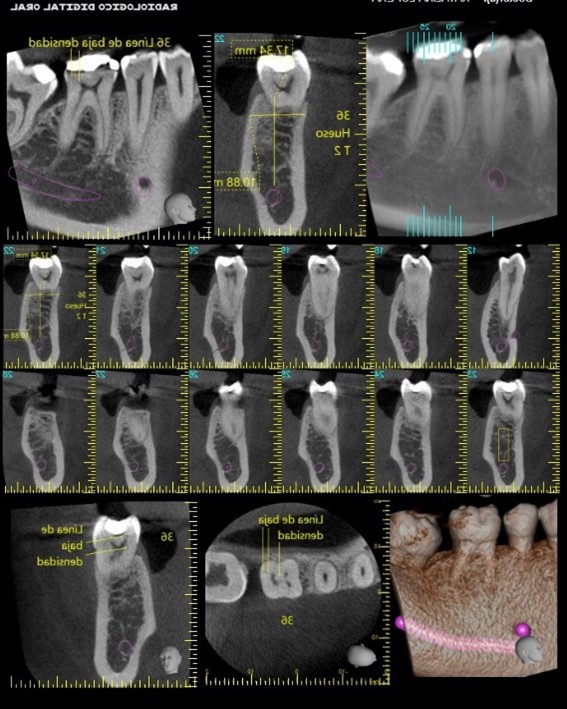

En este caso, se le realiza tomografía al paciente en zona del 36 y al realizar rotación de 360° del diente sobre su propio eje, hay línea de baja densidad en sentido vertical y oblicuo en cara distal y levemente hacia lingual en la corona y tercio cervical radicular, desde la cámara pulpar hacia distal del molar, compatible con fisura por fractura radicular y de la corona, no desplazada en 36. Descartada la posibilidad de estar frente a un artefacto tomográfico. Por eso la evaluación clínica es muy relevante en este caso.